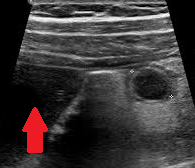

Polycystic liver disease. Red arrow. Infected hepatic cyst (Courtesy Dr. V. Penopoulos)